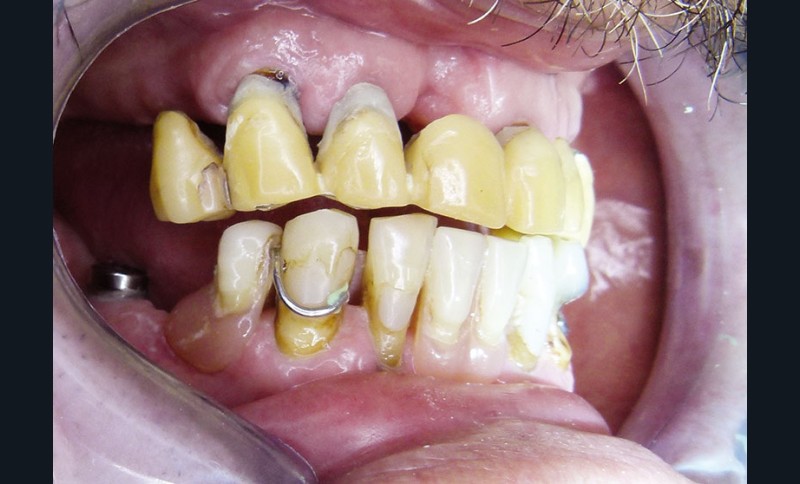

Monsieur L… se présente en décembre 2012 pour une demande de réhabilitation complète de sa cavité buccale. Il est âgé de 65 ans. Il présente un bon état de santé générale, sans pathologie restrictive. En revanche, son état bucco-dentaire est pour le moins problématique … Il est porteur de prothèses provisoires qui se sont délitées avec le temps. Plusieurs implants ont été mis en place auparavant, à la mandibule. Les restaurations d’usage n’avaient jamais été réalisées … (fig. 1 et 2).